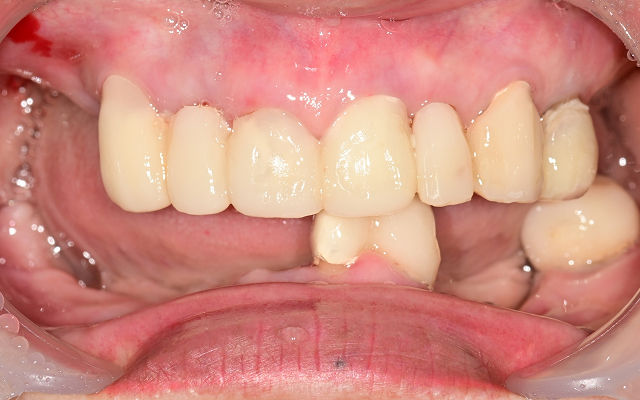

전악 케이스

- 상·하악 전체 보철 설계를 통해 정확한 교합(물림) 회복

- 심미·발음·저작 기능을 종합 고려한 자연스러운 전악 임플란트